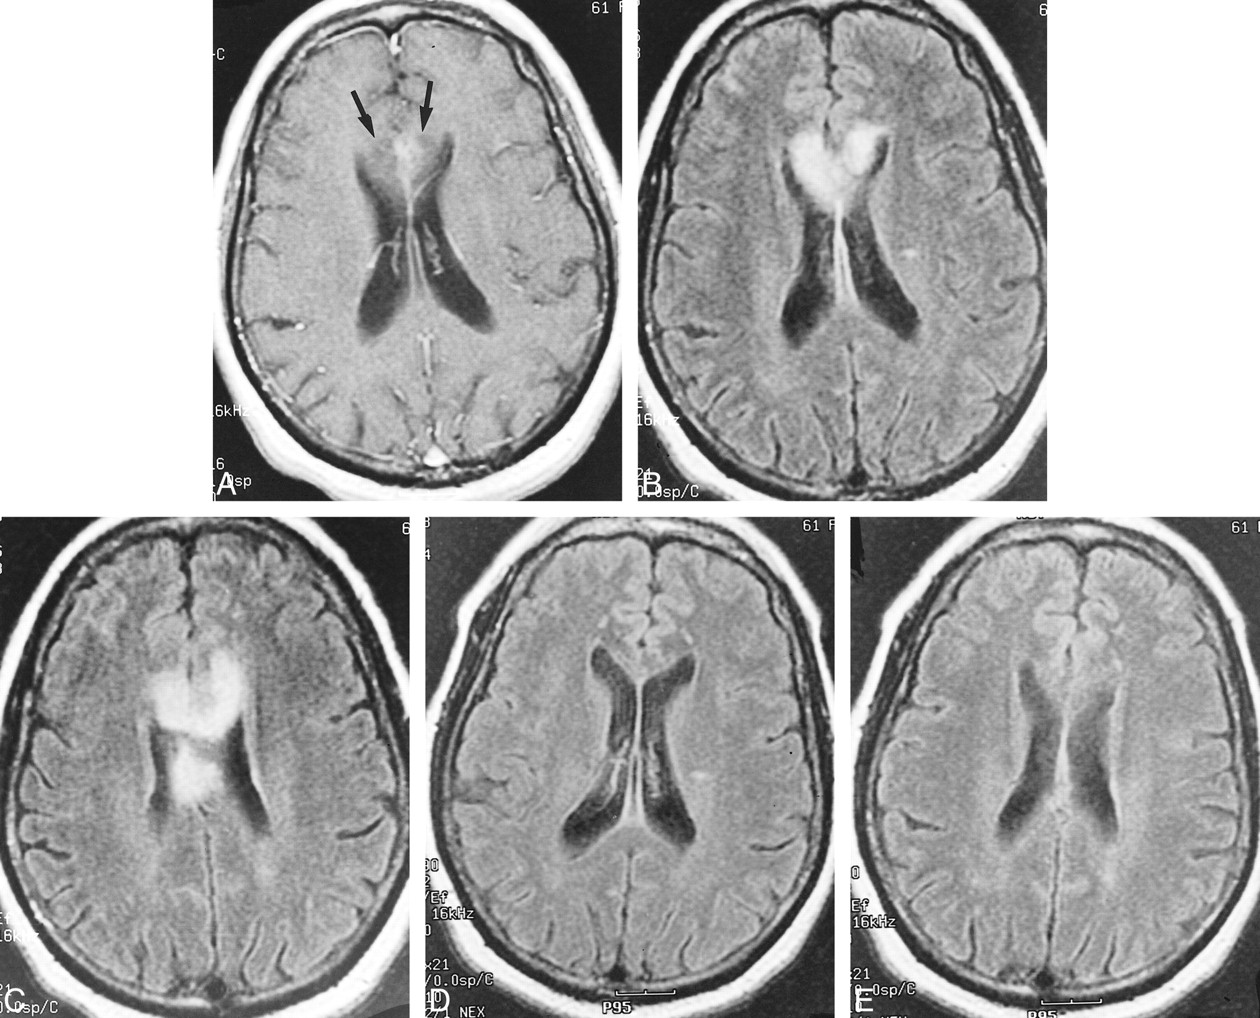

A 61-year-old woman with a long history of hypertension and insulin-dependent diabetes mellitus was in her usual state of health, when 2 to 3 weeks prior to admission, she developed slurred speech, difficulty with handwriting, and right-sided weakness. Her physical examination was significant for a 20% to 30% motor deficit of the right lower extremity. Initial non-contrast CT performed upon admission showed a low-density lesion extending across the genu of the corpus callosum, with mild mass effect on the frontal horns that, given the clinical findings, was considered the causative lesion. Contrast-enhanced MR imaging performed 2 days later showed subtle enhancement on the postcontrast T1-weighted images (Fig 2A) and abnormal high signal intensity on the fluid-attenuated inversion recovery (FLAIR) and long-TR images (Fig 2B and C) within the genu and body of the corpus callosum. The patient returned 3 weeks later for follow-up MR imaging. FLAIR images from that study (Fig 2D and E) showed almost complete resolution of the callosal signal abnormality. MR angiography was performed, which showed markedly small anterior cerebral arteries relative to the other cerebral vessels.

Case 2. Postcontrast axial T1-weighted image (A) (500/20/1) shows subtle enhancement with surrounding hypointensity within the genu of the corpus callosum (arrows). FLAIR images (B, C) (8900/140/1) show abnormal increased signal within both sides of the genu and body of the corpus callosum. Axial FLAIR images (D, E) (8900/140/1) from follow-up MR imaging performed 3 weeks later showed almost complete resolution of the abnormal signal within the corpus callosum